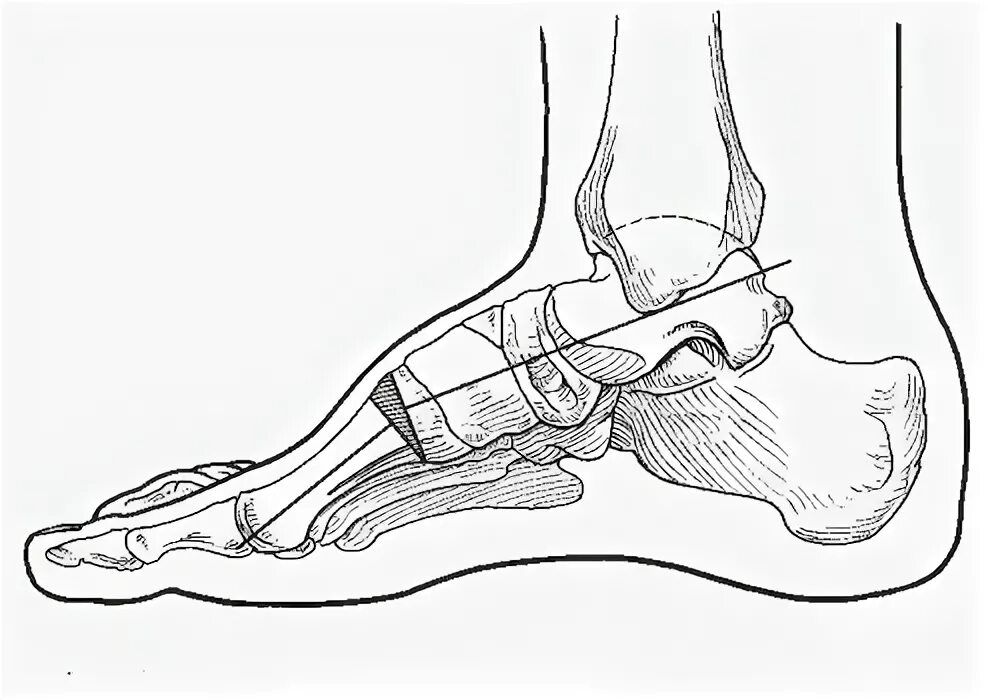

Пяточная остеотомия